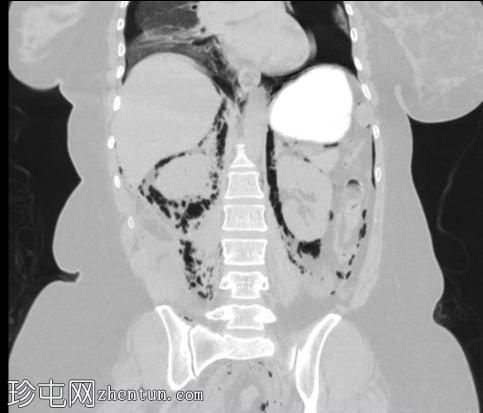

3.jpg

轴位

食管下三分之一处管壁均匀增厚,可见气泡(穿孔起始部位),纵隔及双侧胸膜腔内可见游离气体,提示食管穿孔。

十二指肠内可见造影剂早期渗漏至十二指肠旁间隙(第二个穿孔部位),同时主动脉旁、结肠旁、肾周及膈下区域可见游离气体,提示十二指肠穿孔。